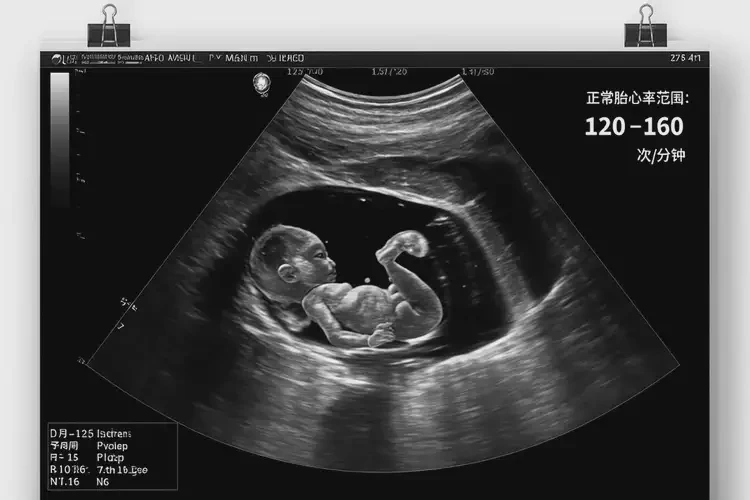

懷孕2個多月時,正常胎心率應在120-160次/分鐘之間。胎心率87次/分鐘明顯低于正常范圍,可能提示胎兒存在缺氧或其他健康問題。僅憑一次胎心率測量結果不能直接決定寶寶是否能要,因為胎心率可能受到多種因素影響,如胎兒睡眠狀態(tài)、孕婦體位等。

• 懷孕2個多月時,正常胎心率應在120-160次/分鐘之間。

• 胎心率低于120次/分鐘或高于160次/分鐘都可能提示異常。

懷孕2個多月胎心率87寶寶還能要嗎(圖1)